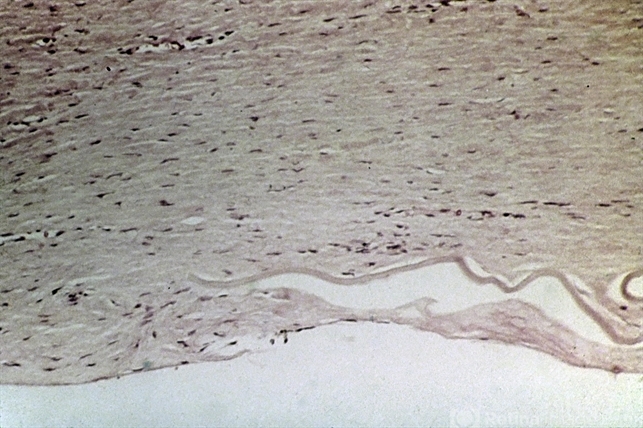

- regraft, retrocorneal membrane, descemet's membrane

- Regraft. A retrocorneal membrane is present posterior to Descemet's membrane.